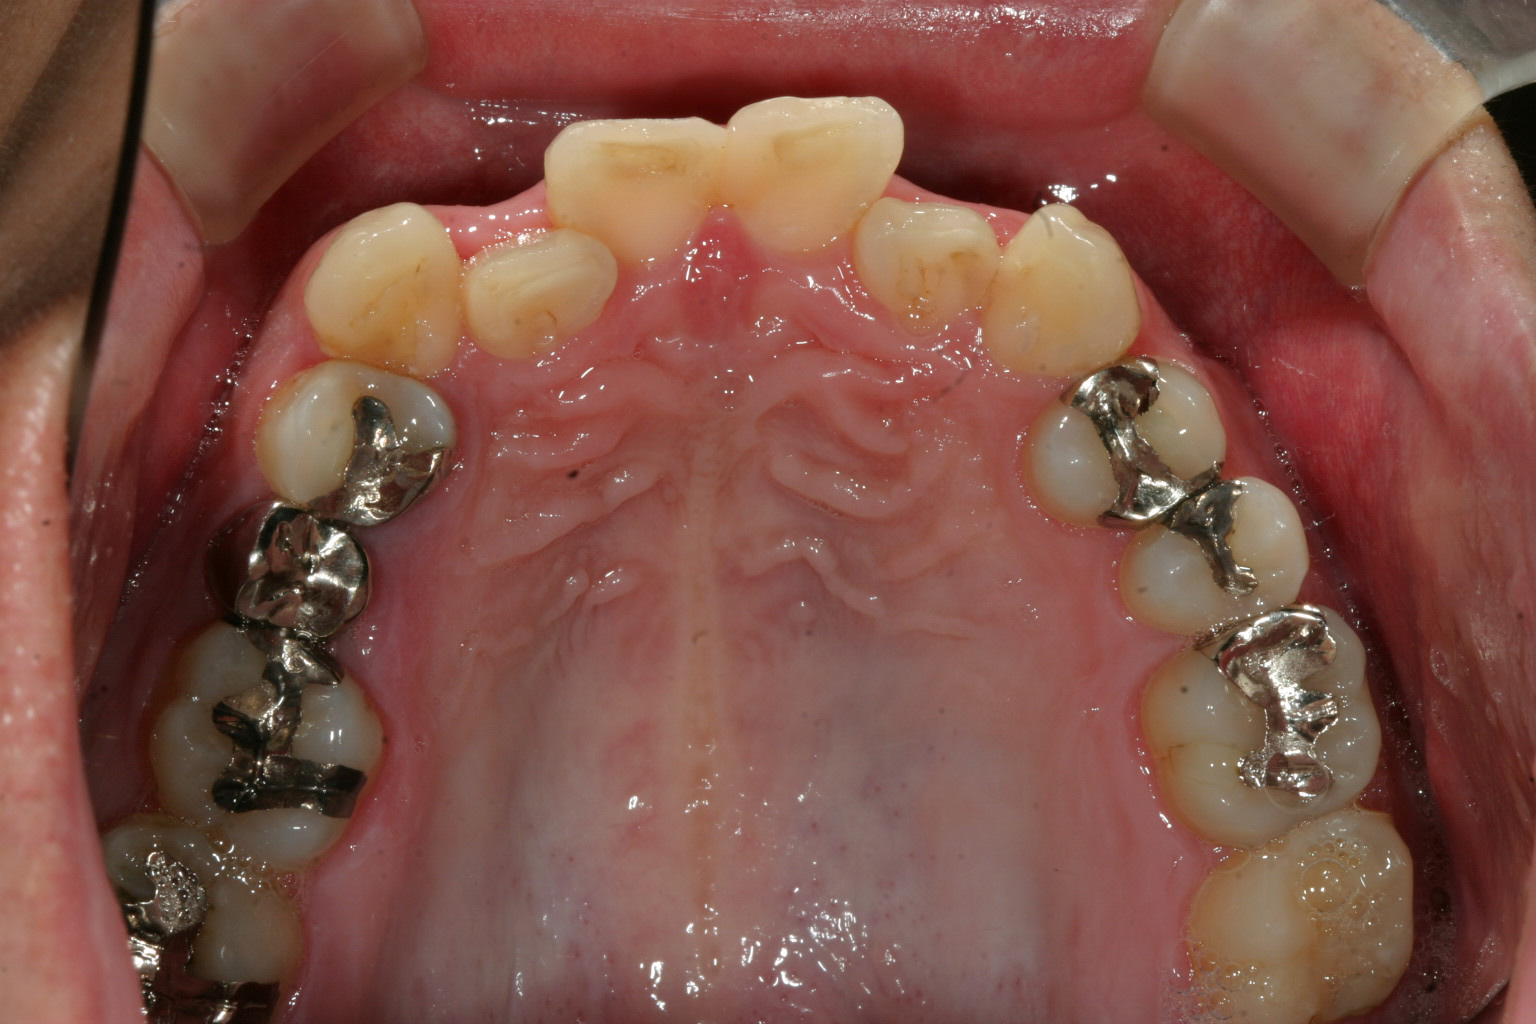

前歯がガタガタしていて見た目も悪く、又食べ物がつまる。

前歯が結構飛び出し歯磨きもしにくいみたいです。

下の顎も飛び出していますね!

インビザラインによる叢生と過蓋咬合の改善例です。

この様な歯列で生活されてますと食後に一定の場所に食物残渣が溜まり、ばい菌が繁殖し歯周病、虫歯等に罹患する可能性が増します。